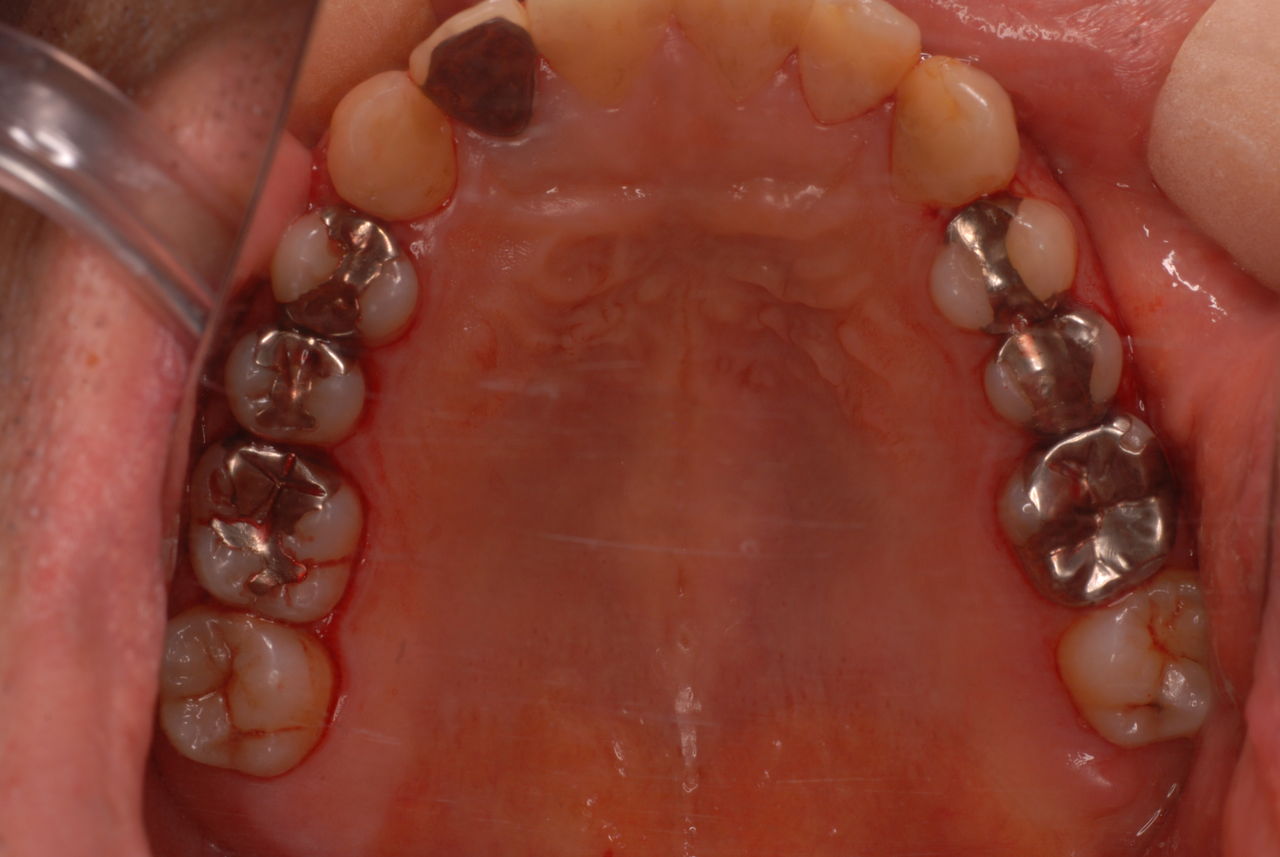

今日のすべての患者さんは、一人を除いて新患を含めてすべて歯周病の方でした。

歯周病は殆どの方に存在し、気づかないうちに進行していきます。

なかなかブラシの使い方ができていないようで、歯磨きと歯周病でのブラシの使い方は別なのですが、習ったことも検査もされずに金属を被せたりしているようで、これからも歯医者さんで抜かれたり、その後にインプラントのような高価な“クギ”を打ち込まれる方が増えるかと思うと残念です。

まず検査をして、ブラシの使い方を習得して歯医者さんで削ったり抜かれたりしないように予防に注意する方々が増えないかと思う日々です。

被せても、詰めても病気は治らないのですから。又病気の元になり易い不適合な差し歯や金属、インプラントがあればそこからバイキンが侵入して体に悪さもしやすいのではないかと心配しています。

全身にバイキンが周り病気の原因になるというのに気づかない方が多いのです。